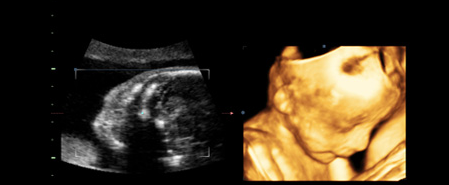

三维彩超是立体动态显示的彩色多普勒超声诊断仪,它的作用和普通的彩超一样,彩超简单的说就是高清晰度的黑白B超再加上彩色多普勒。

泉州福兴妇产医院医师表示:目前22-26周的排畸检查,大多孕妈都选择四维彩超。三维彩超和四维彩超的区别主要在于在一个“时间维”,也就是说,三维彩超是图片,是静态的。

四维彩超是录像,是动态的,可以让孕妈妈看到胎儿一连串的动作,三维彩超只能是某个时间点上的照片,四维彩超的就可以做成DV那样连续的,可以刻录光盘。

准爸妈们通过四维彩超,不仅可以看到宫内胎儿打哈欠、伸懒腰、吮手指等等好看的动作,还能够多方位、多角度观察宫内胎儿的生长发育情况,为早期诊断胎儿先天性体表畸形、先天性心脏疾病提供有效的科学依据,并可以直观的观测胎儿实时动态活动图像。

美国GE-E8四维数字彩超超越了传统超声的限制,全面升级的技能能够显示您未出生宝宝的实时动态活动图像,一样的排畸,不一样的临床效果。较三维彩超更清晰真实,其出色的人体工程学设计能直观、立体的观察和显示人体器官的动态和三维结构。